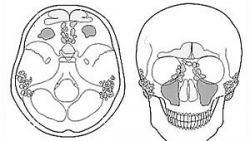

Nebenhöhlen Neben den oben bereits angesprochenen Anteilen der Atemwege (Nase, Mund, Nasen-Rachen-Raum, Kehlkopf, Luftröhre, Bronchien usw.) befinden sich im Schädel noch einige weitere luftgefüllte Hohlräume. Sie alle haben eine Verbindung zum Nasen-Rachen-Raum und dienen u.a. als Resonanzraum für die Stimme und zur Anfeuchtung, Erwärmung und Reinigung der Einatemluft.

Die wichtigsten Nasennebenhöhlen sind:

- die beiden Kieferhöhlen, die links und rechts der Nase im Oberkiefer gelegen sind,

- die Stirnhöhlen oberhalb von Nase und Augenhöhlen,

- die Keilbeinhöhle hinter der Nase, oberhalb des Nasen-Rachen-Raums,

- sowie die Siebbeinzellen links und rechts der Nase oberhalb der Kieferhöhlen.

Weiter muss noch auf die Mastoidzellen hingewiesen werden, die sich hinter den Ohren befinden und mit dem Mittelohr in Verbindung stehen.